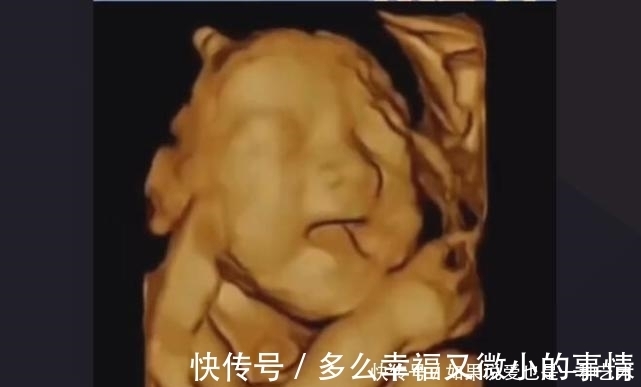

文章插图